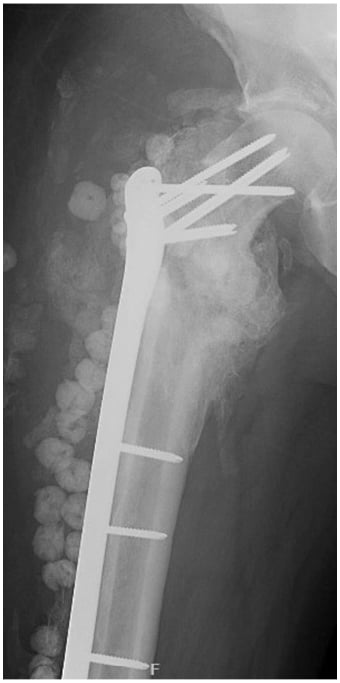

Serial X-rays showed continued fracture healing until March 2022, when the patient returned to the ED with swelling and erythema. A CT scan showed a fluid collection and a healed fracture (Figs. 4, 5), at which point he underwent repeat debridement and hardware removal.

Figure 4: X-rays reveal interval healing of the right hip.